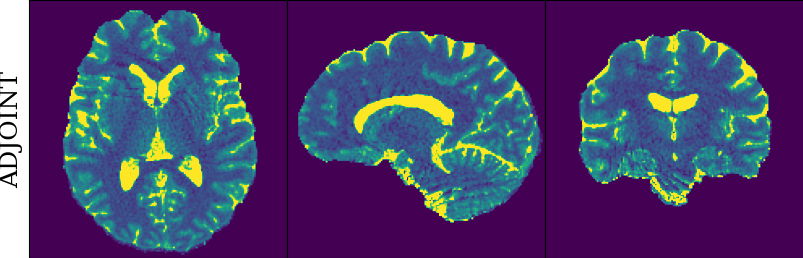

To monitor performance progress, we mapped TSMI to Q-Maps every five epochs. To mitigate the lengthy processing times associated with Dictionary Matching, we implemented a fully connected network to directly map TSMI to Q-Maps [5], significantly reducing processing time. However, for the final assessment, we employed DM on all techniques at the conclusion of the training process (epoch 500). We report in Table 1 the Mean Average Percentage Error (MAPE) of T1/T2 maps, and Peak Signal-to-Noise Ratio (PSNR) and Structural Similarity (SSIM) Index for T1/T2 and normalised PD. To accompany these metrics we also offer in Fig. 2 the reconstructed T1 and T2 maps for the different approaches.

The training and validation loss (Fig. 1) served as valuable guides for architecture and training design. To demonstrate this, we selected a subset of experiments in which we kept certain variables fixed and only modified the one under inspection. From Fig. 1 (a)-(d), MAPEs curves show there is a clear setting with the preferred performance. Specifically, from Fig. 1a, it is evident that using DRUNet yields a clear improvement over the original architecture. This could be attributed to the utilisation of residual units in addition to other architecture differences, such as the choice of upsampling operator (transpose convolution for DRUNet and trilinear for DIP). The choice of input (Fig. 1b) demonstrated a consistent pattern among the tested options, with low rank (conjugate gradient) initialiser marginally outperforming the others. Fig. 1cshows that by epoch 100, stochastic approaches exhibit lower reconstruction errors compared to non-stochastic methods. For example, adaptive LR with stochastic training yields a combined MAPE of 61.40% (17.09% T1 and 44.31% T2) vs. 213.69% (35.50% T1 and 178.19% T2) for the non-stochastic method. This fast convergence is due to adaptive LR and stochastic updates across coils. Despite similar execution times ( 34 min for stochastic with adaptive LR vs. 32 min for non-stochastic with fixed LR), the rapid error reduction makes StoDIP more attractive for training.. To assess the early stopping of DIP models, a key element, we present Fig. 1d. The original work by Ulyanov et al. [21] used 2k iterations, while Hamilton et al. [12] used 30k. In contrast, our settings show StoDIP achieving competitive performance in under 500 epochs (4k iterations) on the entire volume. However, StoDIP can overfit to k-space measurements, affecting reconstruction accuracy, and thus the iteration at which it stops could have a greater impact. We show that adding a spatial penalty term addresses overfitting and instabilities. This is supported by the maps in Fig.2, supplementary material Figures 1-3, and metrics in Table 1. StoDIP reconstructions lack aliasing artifacts, and the TV regularizer (StoDIP + TV) further improves Q-Map reconstruction by reducing checkerboard artifacts observed in StoDIP outputs alone.